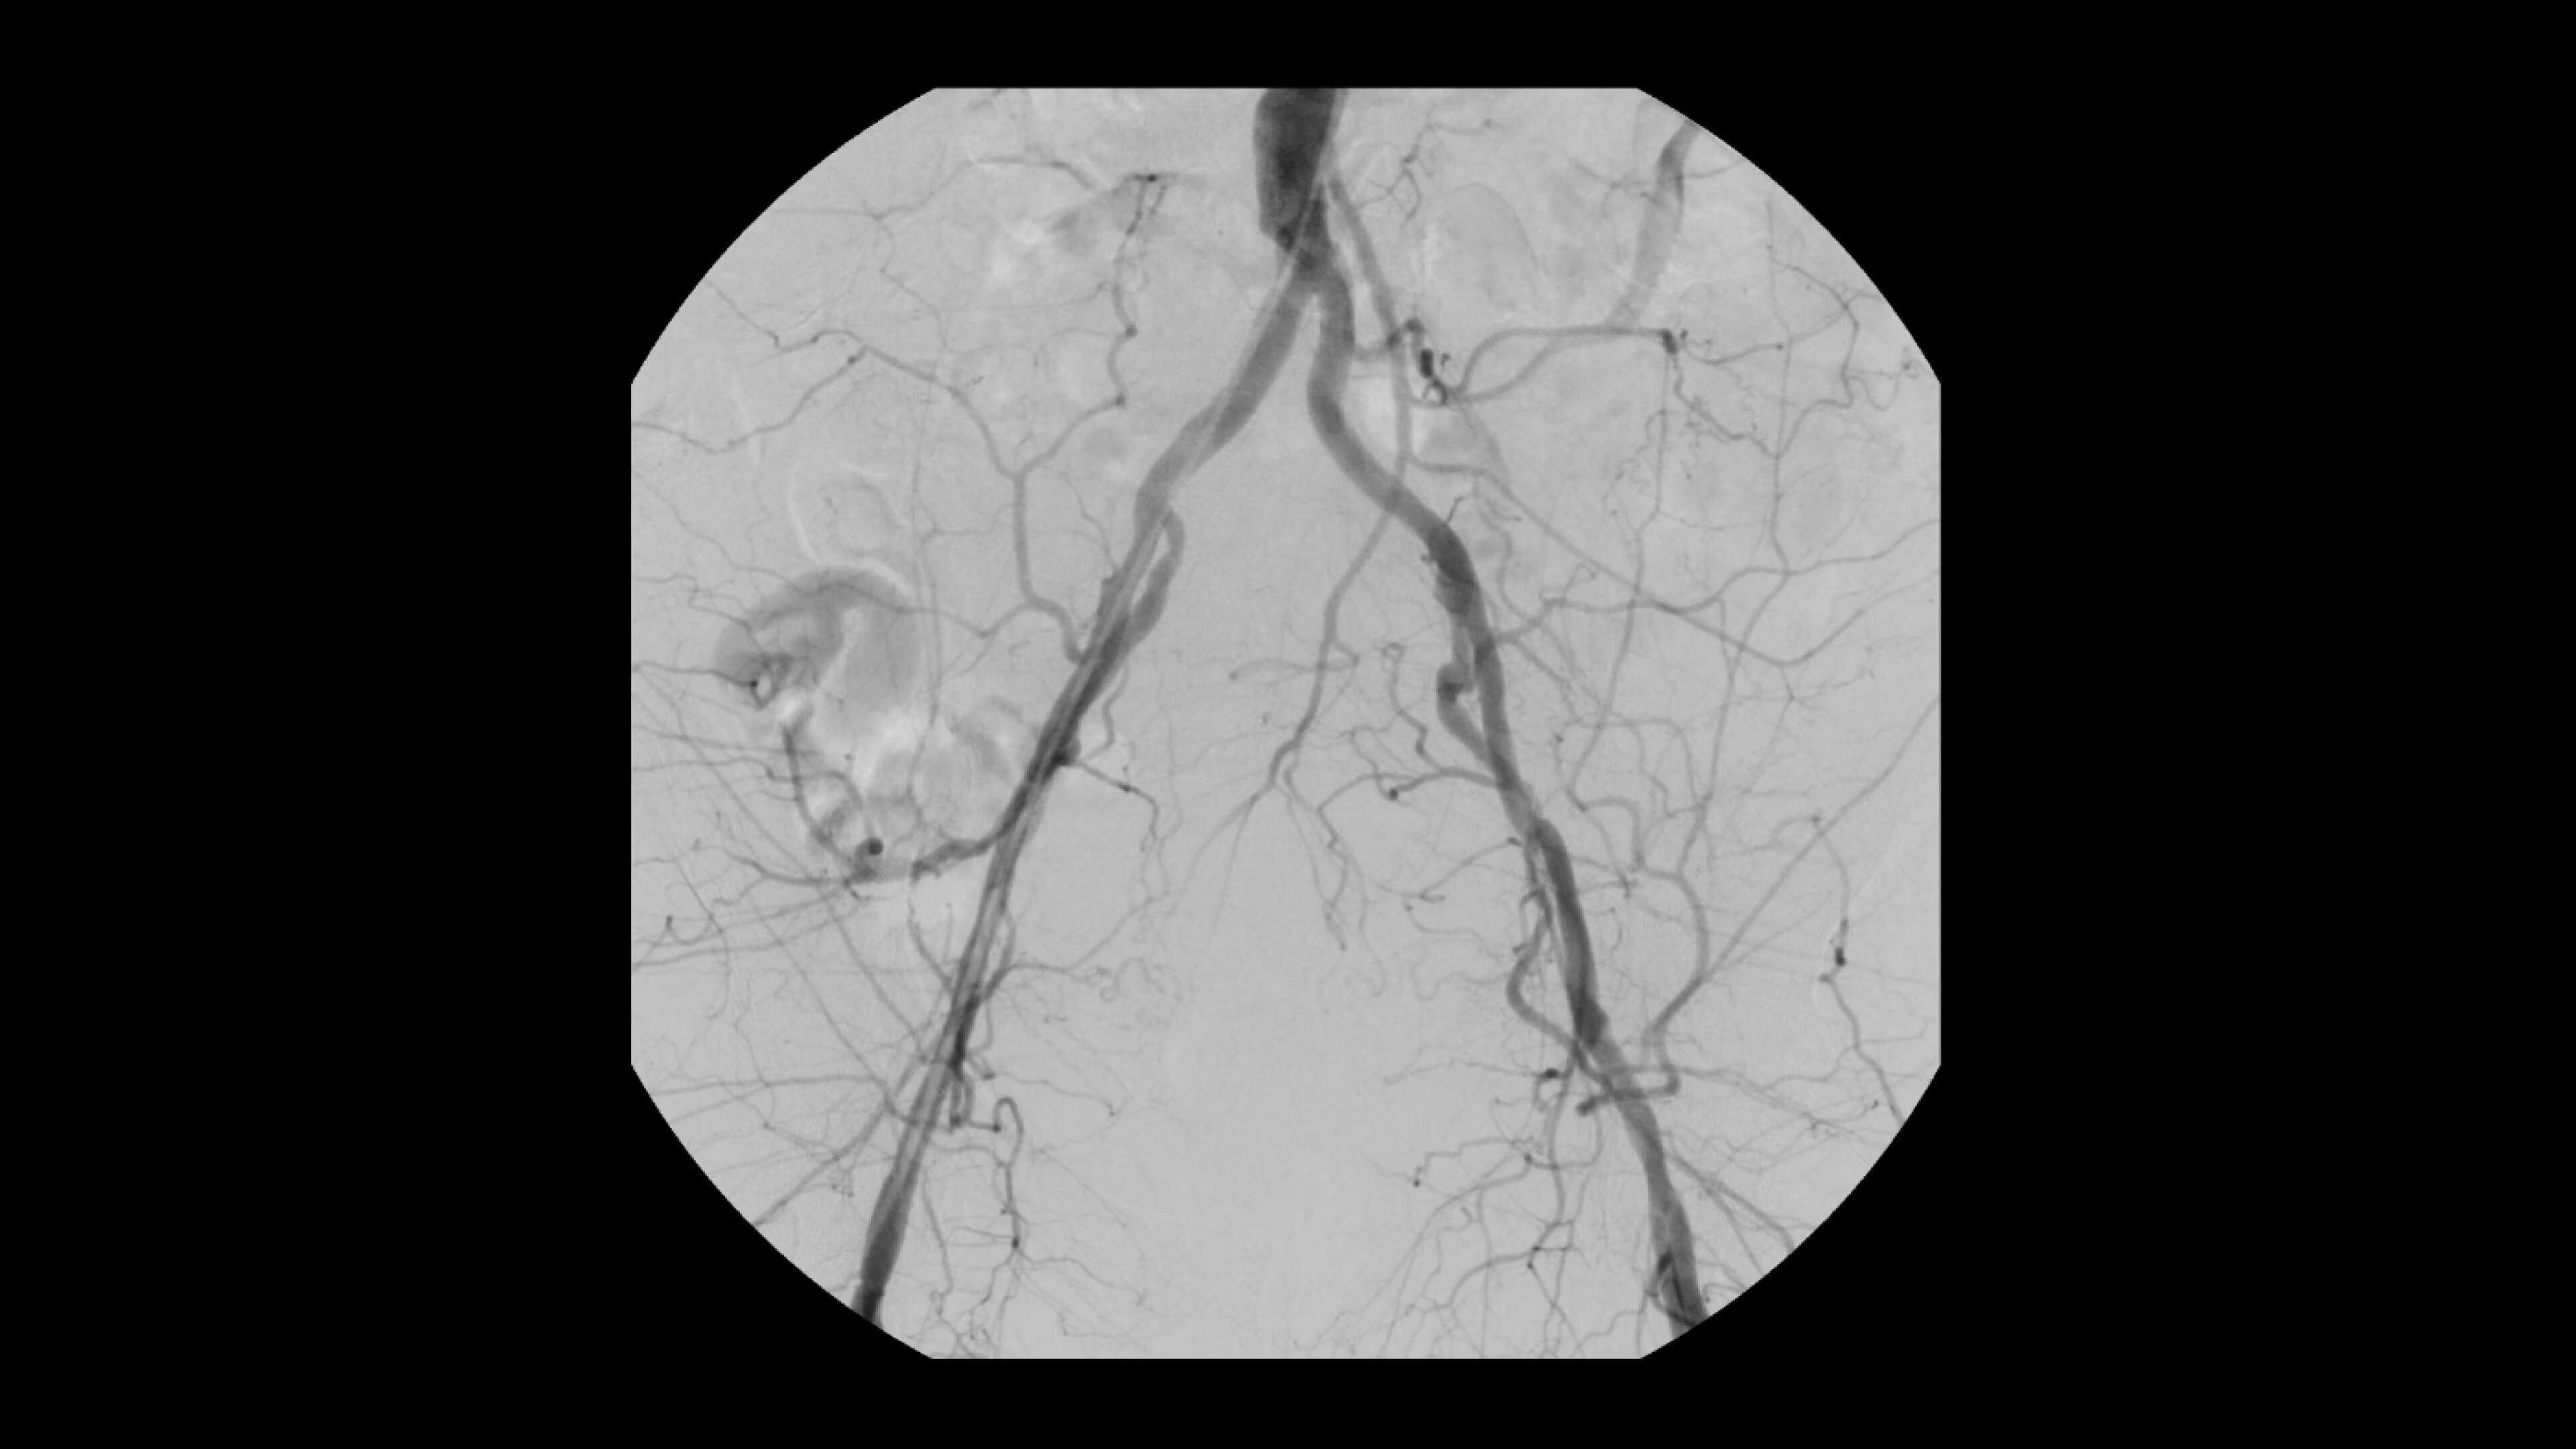

See 0.014” guidewires in chest and abdomen region or 0.008” guidewires in peripheral vascular on a large 4K display.

Interventional procedures require powerful imaging systems. OEC premium

C-arms perform in a variety of procedures such as:

• Prostatic Artery Embolization (PAE)

• Uterine artery embolization

• Pelvic congestion treatments

• Genicular artery embolization

• Venous leak embolization